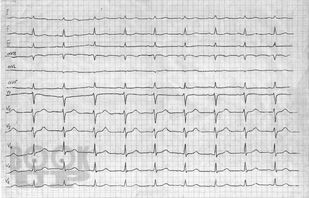

Структура рабочей тетради, составленной коллективом преподавателей кафедры патологической физиологии ФГБОУ ВО ЧГМА, соответствует тематике занятий по разделу «Патология сердечно-сосудистой системы» дисциплины «Патологическая физиология. Клиническая патофизиология», содержит задания для самоподготовки, ситуационные задачи. Рабочая тетрадь предназначена для подготовки к практическим и лабораторным занятиям и для самостоятельной аудиторной работы студентов, обучающихся по специальностям 31.05.01 Лечебное дело и 31.05.02 Педиатрия.